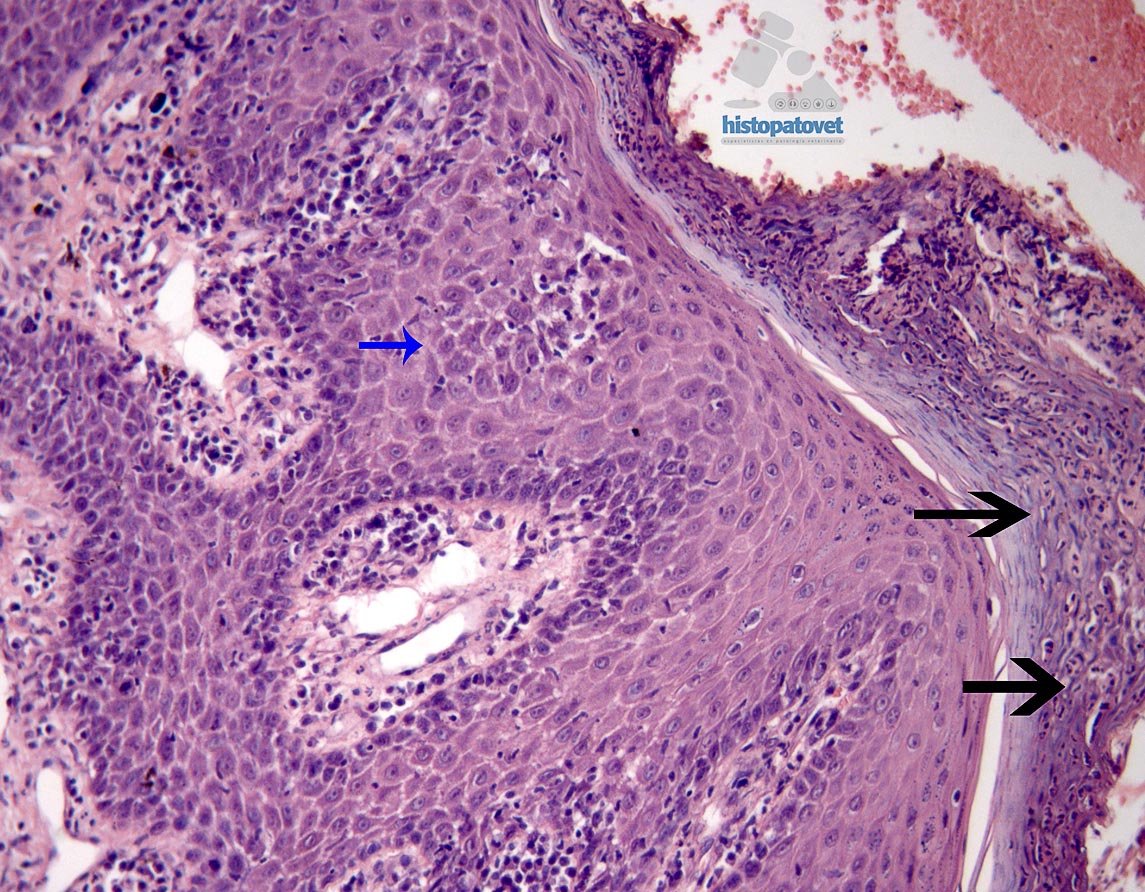

Se reciben dos pequeños punchs dérmicos. La epidermis, presento una hiperqueratosis ortoqueratótica con formación de costras( Fig4.).

En varias partes los queratocitos muestran palidez, con zonas de degeneración, provocando necrosis y separación de ellos. Como consecuencia se formaron cavidades( pústulas), con presencia de polimorfonucleares y queratocitos libres(Fig5. y 6.).

Los hallazgos histopatológicos son de una enfermedad autoinmune del grupo de los pénfigos. Los cambios morfológicos son similares a los descritos en el PÉNFIGO FOLIÁCEOS, con una presentación predominantemente NASAL.

Pénfigos foliáceos es una enfermedad PUSTULAR. Sin embargo, la lesión puede empezar como una pápula, para luego de forma rápida convertirse en pústula. Posteriormente provoca erosiones y costras. Por esto, la principal muestra diagnóstica especialmente para histopatología, en una pústula intacta. Tengan en consideración que este paciente ingreso por una lesión costrosa en el plano nasal, es decir la fase clínica pustular ya había pasado, sin embargo fue posible verla histológicamente.

Cuando sucede un impedimento en la adhesión o unión de los queratocitos, esto provoca la separación de las células, causando un fenómeno conocido como ACANTOLISIS.

En general en el caso de pénfigos foliáceos, los auto anticuerpos actúan contra los antígenos presentes en la desmogleina-1 y otras moléculas de adhesión celular.